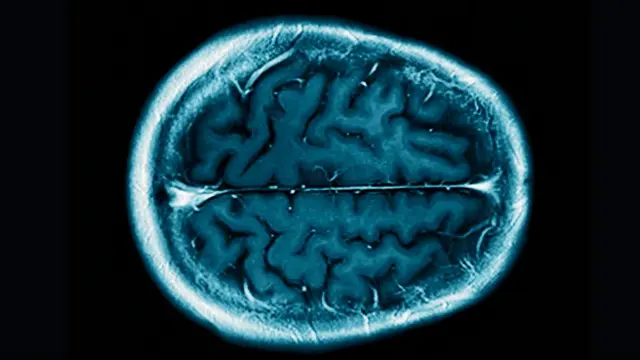

До сих пор ученые успешно использовали различные методы нейровизуализации, такие как функциональная магнитно-резонансная томография, чтобы установить, в сознании ли парализованные или находящиеся в вегетативном состоянии пациенты.

Однако МРТ - довольно громоздкий и дорогостоящий метод (час использования обходится в десятки тысяч рублей), поэтому Бирбаумер со своими коллегами испробовал другой вариант - спектроскопию в ближней инфракрасной области, которая позволяет отслеживать изменения обмена веществ путем наблюдения за кровотоком.

БИК-спектроскопия применяется с 1980-х годов для выявления участков мозга, связанных с когнитивными функциями, такими как регуляция моторики и язык.

Бирбаумер заметил, что кровоток в мозге парализованных пациентов менялся в зависимости от того, каким был его мысленный ответ на заданный вопрос – "да" или "нет".